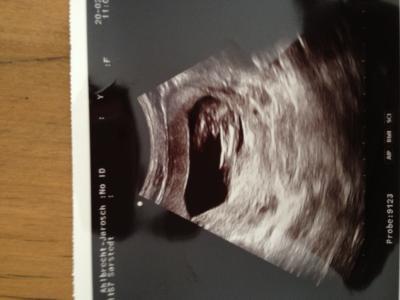

Hallo ihr Lieben! Ich bin ssw 15+4 und komme eben vom Arzt! Er meint es könne ein Junge sein, oder die Nabelschnur !? Ich erkenne nicht wirklich etwas! Wer gibt mir bitte seine Einschätzung ?! Lieben dank im voraus .... :-)

Bild zu Ist es ein Junge oder ein Mädchen? - Babys 1. Lebensjahr

Hallo, Würde auch eher vorsichtig auf Junge tippen. Hatten ein aehnliches Ultraschallbild, allerdings in einer späteren SSW (etwa 20 SSW). Beim nächsten Ultraschall bekommst du bestimmt mehr Gewissheit, ob es ein Junge oder ein Mädchen wird. Alles Gute

Also ich sehe da garnix